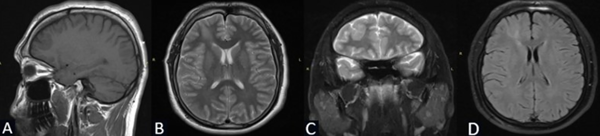

Se solicita RM de cerebro con contraste de cortes de 1 mm donde se objetiva lesión espontáneamente hipointensa en la secuencia T1 localizada en la región frontal derecha entre F1 y F2 de 3 x 2.25 x 2.84 cm. Hiperintensidad de la sustancia blanca subcortical en T2 de forma triangular con base hacia la corteza y vértice hacia la región ventricular (signo del transmanto), engrosamiento cortical focal, pobre delimitación entre la sustancia blanca y gris. Sin efecto de masa y escaso realce tras la administración del contraste (Figura 1).

Figura 1. Caso 1: RM de cerebro. A) Secuencia T1. Corte sagital. B) Secuencia T2. Corte axial. C) Secuencia T2. Corte coronal. D) Secuencia T1 con contraste. Corte axial.